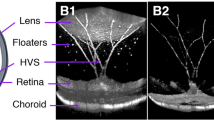

In vivo OCT imaging of the USH2AKO rabbit model

High-resolution spectral domain optical coherence tomography (SD-OCT) imaging was employed to visualize the progression of RP USH2AKO rabbits. Figure 1 presents 2D OCT images obtained at different time points along the scanning line indicated in Fig. 1f, illustrating the advancement of the syndrome. The control wildtype (WT) image (Fig. 1a) displays a normal retinal architecture with distinct layers, including the internal limiting membrane (ILM), retinal vessels (RVs), choroidal vessels (CVs), sclera, ellipsoid zone (EZ), and retinal pigment epithelium (RPE) layers. In contrast, significant disruption to the EZ layer was observed in the USH2A model at 4 months (Fig. 1b–e). The disruption and degeneration of the EZ layer progressed up to 12 months during the monitoring period. Figure 1f–g showcases en face 3D volumetric OCT images, where the entire optic nerve, RVs and EZ degeneration are clearly visualized with high resolution and contrast. Additionally, Fig. 1h represents a selective single orthogonal image from among the 512 B-scan images to provide a 3D volumetric representation. The EZ degeneration area appears as a region of strong OCT scattering when compared to the adjacent tissues. The en face and volumetric OCT images provided detailed information about the retinal architecture, facilitating the identification and analysis of the EZ degeneration areas in comparison to surrounding tissues.

Longitudinal 2D OCT imaging reveals progressive ellipsoid zone (EZ) degeneration in USH2AKO rabbits: (a) Control image showing different retinal layers including RVs, CVs, EZ, RPE, and sclera. (b–e) Images at 4–12 months old, demonstrating persistent EZ degeneration. Noteworthy is persistence and progression of EZ degeneration from 4 to 12 months old. (f) Enhanced 3D OCT volumetric visualization at 12 months reveals optic nerve and RVs location. (g) Orthogonal images from a single B-Scan illustrate the detected EZ area (white dotted circle). (h) En face 3D OCT emphasizes the surface of the EZ region. (i) A graph depicting the quantification of EZ thickness, illustrating the progression of EZ degeneration over time. The data is presented as the mean ± standard deviation (n = 3, p < 0.005).

Through segmentation of the images to extract the EZ degeneration area, the thickness of the damaged EZ region was measured using ImageJ software (Fig. 1i). At 4 months, the calculated thickness of the EZ damaged area was approximately 55.87 ± 4.55 µm. By comparing the measurements at different time points, it was observed that the EZ damaged area slightly increased by approximately 32% at 12 months (EZ thickness = 73.77 ± 4.10 µm at 12 month). The EZ damaged area remained almost stable from 6 to 8 months, with a thickness of 57.24 ± 4.10 µm at 6 months compared to 59.40 ± 5.01 µm at 8 months. This information further confirms the ability of OCT to evaluate EZ degeneration in the USH2A syndrome model over the long term.